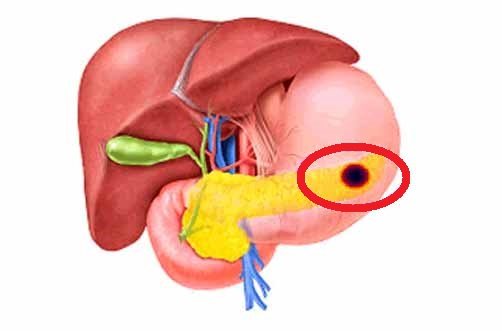

Фотографии медицинских исследований инсулиномы и синдрома Триады Уиппла